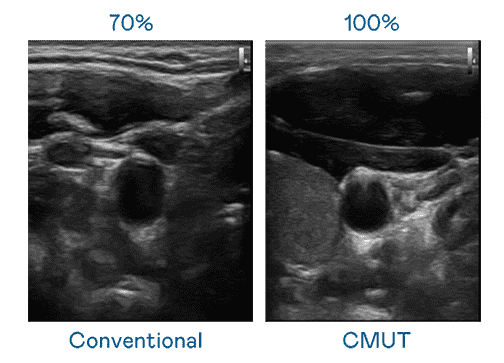

CMUT 技术是一种用电容式微机电元件来产生超音波讯号的技术。。。与传统 PZT 压电式技术相比,,CMUT 频宽增加 30%,,更宽频的超音波讯号让影像解析度大幅提升,,,,是实现高影像品质医疗超音波扫描、、、、促进精准医疗发展的关键技术。。。。

大频宽带来超清晰影像

超音波影像的解析度高低,,,首先取决于探头能发出的讯号频宽。。人生就是博 CMUT 可提供高清晰的超音波讯号,,,,提供高频宽、、、、高灵敏度、、、影像纹理细节更高的超音波影像,,协助医护人员缩短影像判读时间及利用精准的医疗影像进行诊断。。。。